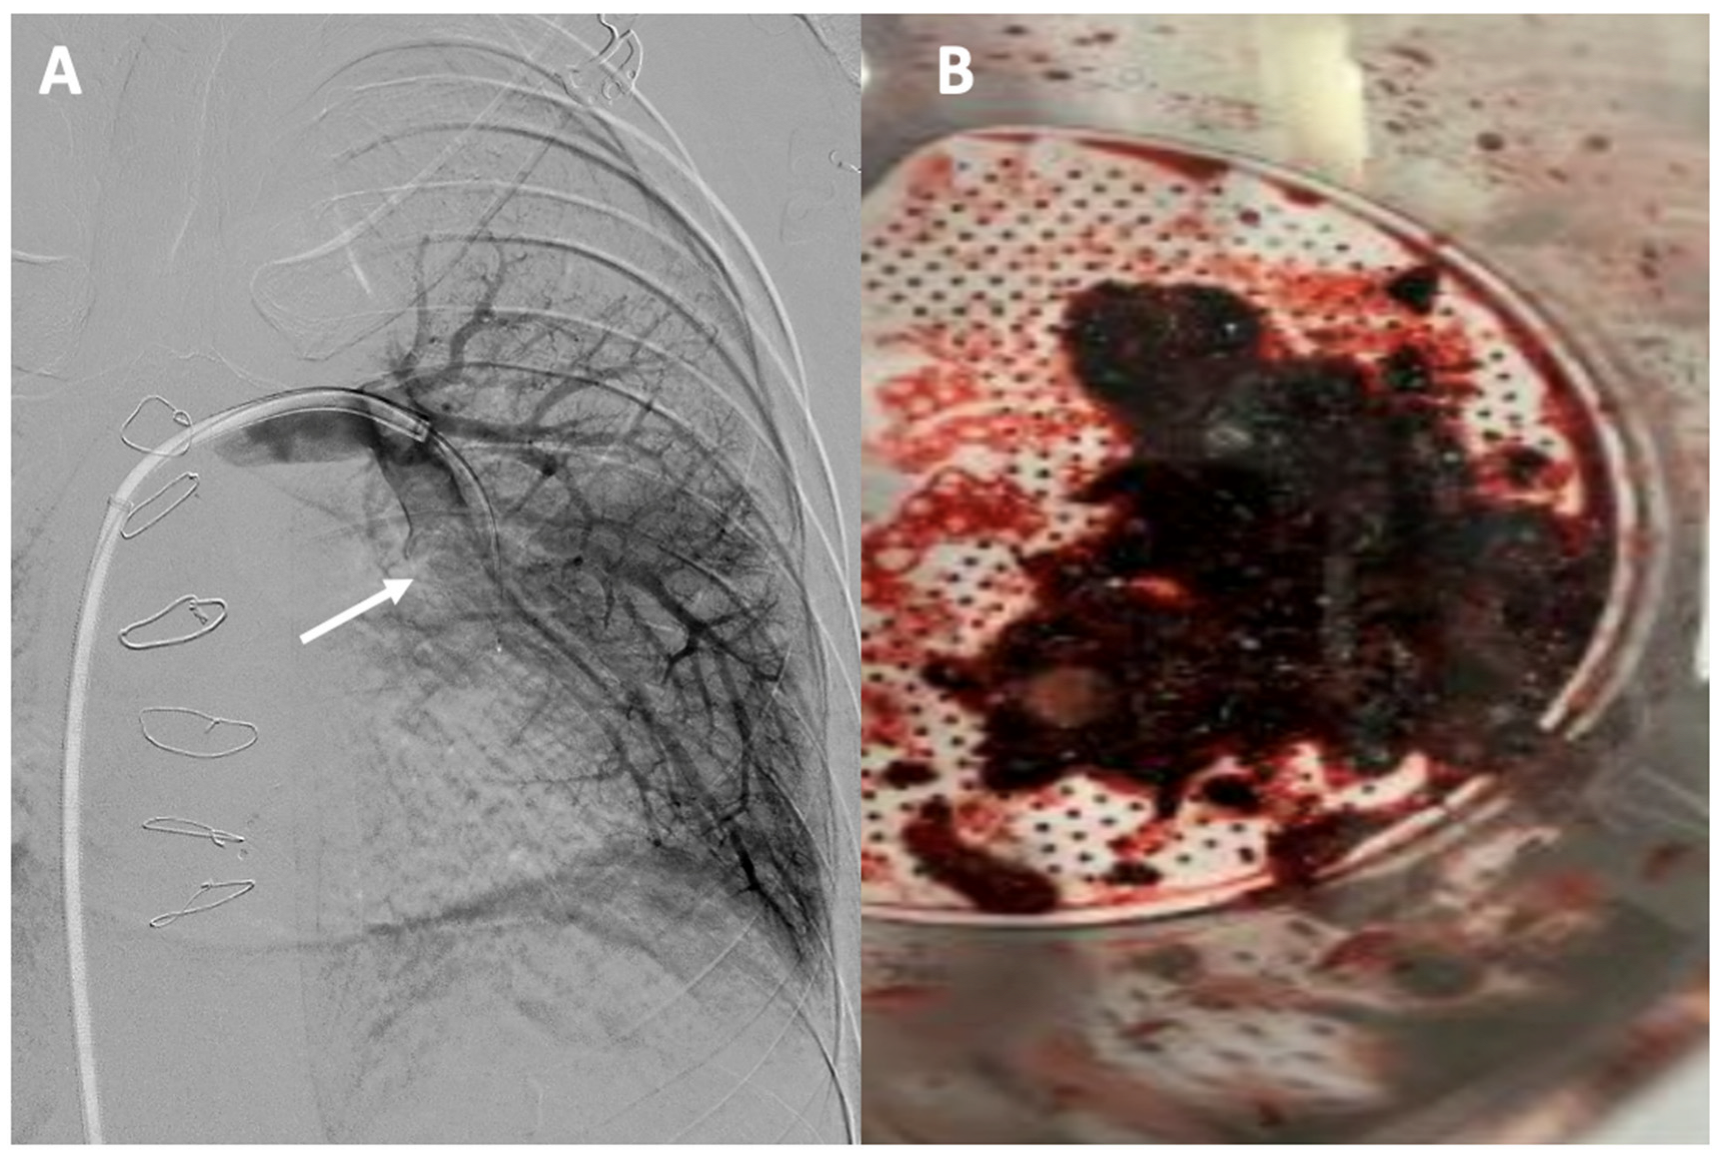

3.5.3. Thrombectomy in Acute Pulmonary Thromboembolic Disease

| Acute Pulmonary Thromboembolic Disease | Mechanical thrombectomy and aspiration thrombectomy may be useful for treating pulmonary embolism in selected cases of Fontan patients. |